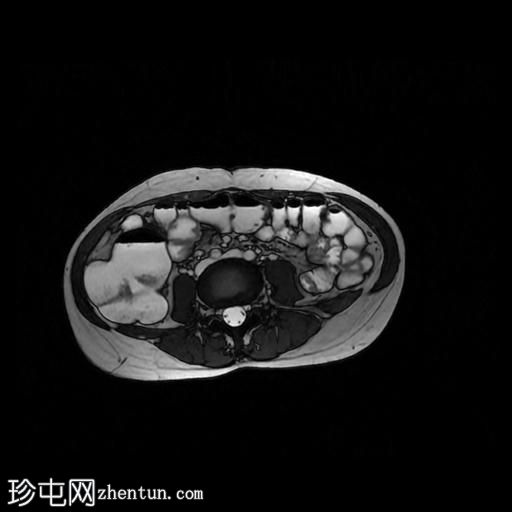

冠状位T2加权像

脂肪抑制

轴位

T2加权像

轴位T1加权像

增强脂肪抑制

冠状位T1加权像

回肠末端及盆腔回肠肠袢可见长段肠壁增厚及强化,肠周血管丰富,呈“梳状征”,并可见明显的纤维脂肪浸润。

未见瘘管、积液、腹水或梗阻。

磁共振肠道造影(MRE)结果支持克罗恩病的诊断,显示远端及末端回肠以活动

性病

变为主,并可见明显的肠周血管。